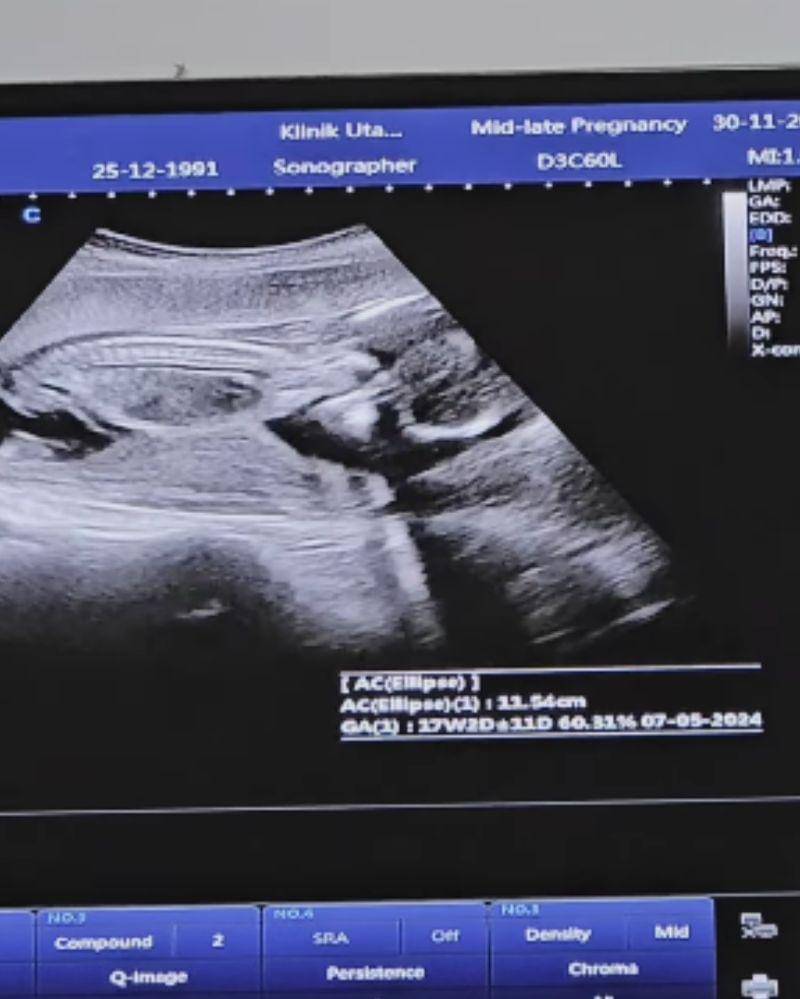

Berdasarkan video yang dibagikan Alyssa ke media sosial miliknya, saat ini kandungannya sudah memasuki usia 18 minggu. Hal ini terlihat jelas pada saat Alyssa menjalani pemeriksaan ultrasonografi pertamanya.

Selain memperlihatkan usia kehamilannya, video tersebut juga menunjukkan bagaimana kondisi kesehatan bayi yang ada di dalam perut Ica saat ini. Mulai dari ukuran hingga suara detak jantung bayinya.

Terakhir, calon anak ketiga Alyssa dan Dude ini diperkirakan akan lahir pada 7 Mei 2024. Hal ini diketahui melalui hasil pemeriksaan yang dibagikan Ica pada video unggahan pemeriksaan pertama kehamilannya.